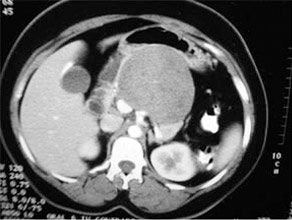

CT Scan of Infected Pancreatic necrosis

ANP is a clinical condition affecting not only the pancreas but other organ systems as well. It can be a dreaded and severely life threatening condition if timely therapy is not instituted. The inherent mortality of this condition again has fallen from 40% to 15% in our centre. Initial therapy of recussitation& conservative management of SIRS needs to be done in an ICU to tide over the first couple of weeks. Intervention (Radiological or Surgical) is requiredto tackle infected Acute Necrotic Collection (ANC) or Walled Of Necrosis (WON).Surgical intervention is generally delayed to atleast 4 weeks if possible so that the necrotic elements separate from the viable pancreas. At times a second or third debridement may also be required albeit rarely.

Common causes include gallstones, alcohol abuse, hyperlipidaemias and idiopathic.